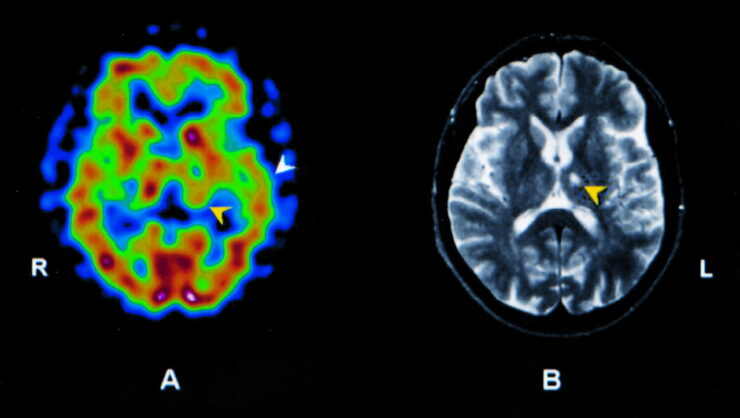

Brain Single Photon Emission Computed Tomography (SPECT) is a sophisticated imaging method that utilizes radioactive tracers to examine and visualize brain function. This nuclear medicine technique allows health professionals to evaluate the physiological processes within the brain, effectively making it possible to gain a snapshot of regional cerebral blood flow and metabolic activity.

Unlike traditional MRI or CT scans, which primarily focus on structural anatomy, SPECT provides critical information about how the brain is working in real-time, thus offering insights into functional abnormalities that may not be apparent from structural imaging alone.

One of the most striking differences between SPECT and other imaging modalities, such as MRI and CT, is the focus on functional rather than structural mapping. While MRI and CT provide detailed images of brain anatomy, SPECT highlights the blood flow and metabolic processes taking place within various brain regions.

This functional information is critical in understanding disorders that exhibit no overt structural changes, such as certain mood disorders or neurodegenerative diseases. SPECT is particularly sensitive to changes in cerebral blood flow and, thus, provides deeper clinical insights during the early stages of disease progression.

The output of a brain SPECT scan is a powerful visual representation of the brain’s functional status. Each region of the brain has specific responsibilities from those controlling motor functions to areas associated with cognition, emotions, and memory.

By assessing regional cerebral blood flow, SPECT can reveal patterns of activation or hypoactivity linked to different neurological and psychological states. For example, elevated activity in certain areas may correlate with mania in bipolar disorder, whereas diminished activity may indicate depressive states.